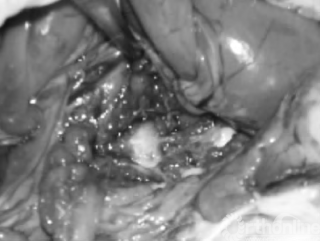

2.1 解剖学观察结果 对照组: 该组各时期椎间盘周缘与毗邻组织无黏连,椎管内无渗血,椎间盘触之质韧。实验组:术后2周: 被注射椎间盘周缘与毗邻组织有黏连,椎间盘触之稍质硬;术后4周: 被注射椎间盘周缘与毗邻组织黏连紧密,不易分离,椎间盘硬度增加(见图 1);术后8周: 被注射椎间盘成骨样硬(7号腰穿针难以刺入) ,椎间盘突向椎管内压迫硬脊膜,脊神经根有黏连,分离困难。椎间盘周缘可见局部骨赘形成,质硬(见图 2) 。

图1 实验组术后第4周肉眼观察,被注射椎间盘周缘与毗邻组织粘连紧密,不易分离,椎间盘硬度增加

图2 试验组术后第8周肉眼观察,被注射椎间盘成骨样硬,间盘突向椎管内压迫硬脊膜,脊神经根有黏连,分离困难。椎间盘周缘课件局部骨赘形成,质硬